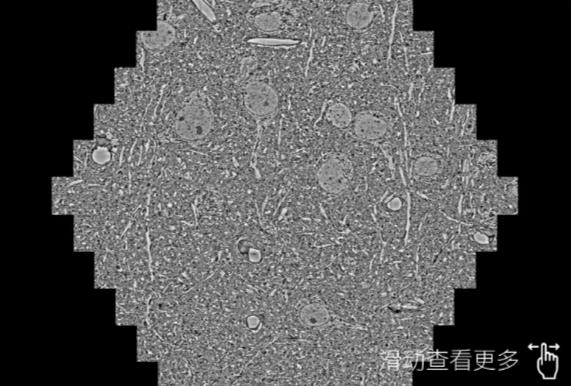

鼠脑切片。左图使用潍坊蔡司潍坊扫描电镜MultiSEM706对165μmx143pm面积区域成像,耗时仅需1.5秒。右图为鼠脑切片中30μm区域放大效果。样品由芝加哥大学B.Kasthuri提供。